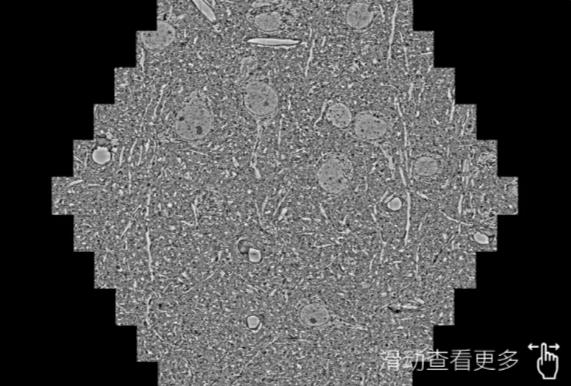

鼠脑切片。左图使用廊坊蔡司廊坊扫描电镜MultiSEM706对165μmx143pm面积区域成像,耗时仅需1.5秒。右图为鼠脑切片中30μm区域放大效果。样品由芝加哥大学B.Kasthuri提供。